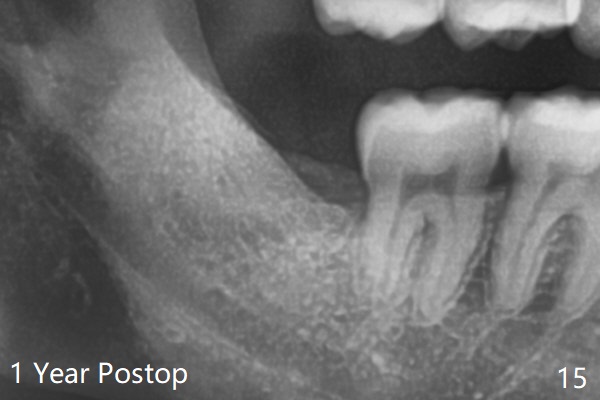

In fact the tooth #32 is extracted first; the defect involves the distobuccal aspect of the tooth #31 (Fig.4 *). An intraop PA is taken after extraction to confirm whether a broken surgical fissure bur tip retains or not; the distal lamina dura of #31 is low (Fig.5 *). It is expected to increase after cocktail bone graft (Fig.5' arrow). As planned, the bone cement (Fig.6 C) and allograft (G) are placed in the distal and mesial portions of the socket; between them is Osteogen Plug (O). Another piece of Osteogen Plug (as collagen membrane for bone graft) is placed on the top of the socket before suturing with 4-0 Plain Gut (Fig.7,7' O). Also note the bone graft being placed distobuccal (CT study) to #31 (Fig.7' red dashed line) to reduce possibility of future periodontitis. The patient returns 15 days postop with chief complaint of mild pain since extraction, although the wound looks normal. The transverse cortex connecting to the lamina dura (Fig.5 *) is obliterated when allograft is placed (Fig.7 G). The part of the graft remains in place 1 month postop (Fig.9) in spite of wound dehiscence (Fig.8). The bone graft loss is indicated by the fact of the reappearance of the transverse cortex (Fig.9). In the same appointment, the tooth #17 (Fig.10) is being extracted (Fig.11), leaving a defect mesiobuccal (Fig.12 *) to distal (curette). Part of Osteogen plug (Fig.13 O) is stretched to cover the mesially placed allograft (Fig.14 G). One quarter of Collagen plug is placed over the Osteogen plug (Fig.13 O) before 4-0 PGA suturing. There is bone regeneration 1 year postop (Fig.15,16).